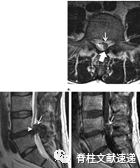

图注:钙化椎间盘及骨赘导致脊液漏

图注:一位47岁女性因钙化椎间盘后方骨赘导致硬脑膜撕裂、脑脊液漏和颅内压过低。

图注:5岁女孩出现症状性儿童钙化性椎间盘炎,颈部疼痛3周,无外伤史。出现斜颈,活动受限。随访6个月后 CT图像显示突出部分的钙化点被吸收,C3/4髓核仅有微小的残余钙化(箭头)。3个月后疼痛几乎完全缓解,6个月随访时疼痛完全缓解。